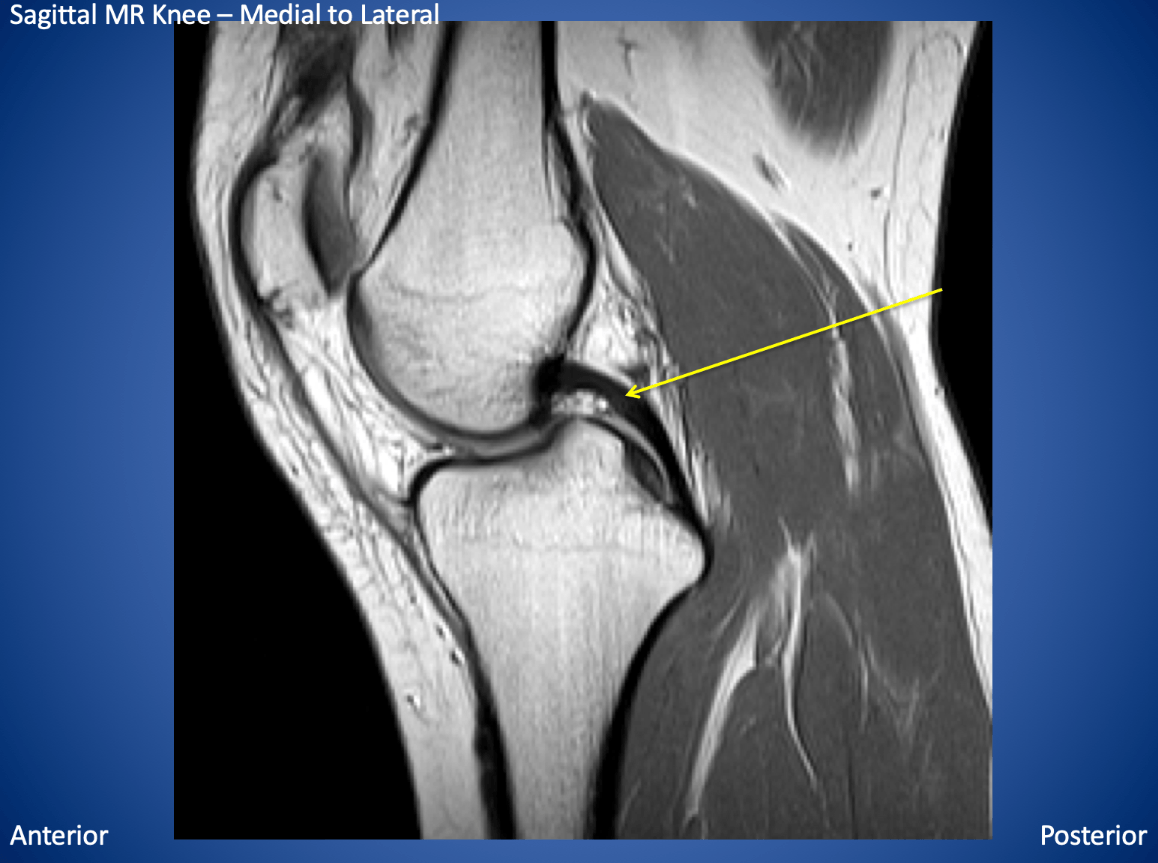

The yellow arrow is pointing to this structure.

What is the posterior cruciate ligament?